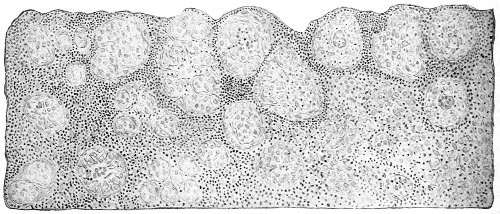

Cysts of the Vulvo-vaginal Glands.—Cysts may 41 occur in the duct of the vulvo-vaginal gland or in the gland itself. Cysts of the duct are small—about the size of a chestnut. They are situated superficially, lying immediately under the mucous membrane of the vagina at the base of the labium minus.

Fig. 18.—Cyst of the right vulvo-vaginal gland (Hirst).

Cysts of the gland may be unilocular if formed at the expense of a single lobule of the gland, or multilocular if several lobules enter into their formation. These cysts may attain the size of the fetal head (Fig. 18).

Cysts of the gland or of the duct are formed by retention of the cyst-contents. The retention is due to occlusion of the duct, usually the result of inflammation. In some cases the duct remains pervious, and the retention is due to the altered character of the secretion of the gland, which becomes too viscous to pass, except under unusual pressure, along the duct.

These cysts contain clear yellow or chocolate-colored 42 fluid. The diagnosis of cyst of the vulvo-vaginal gland is usually not difficult. If we are in doubt in regard to the fluid character of the tumor, this may be determined with the exploring-needle.